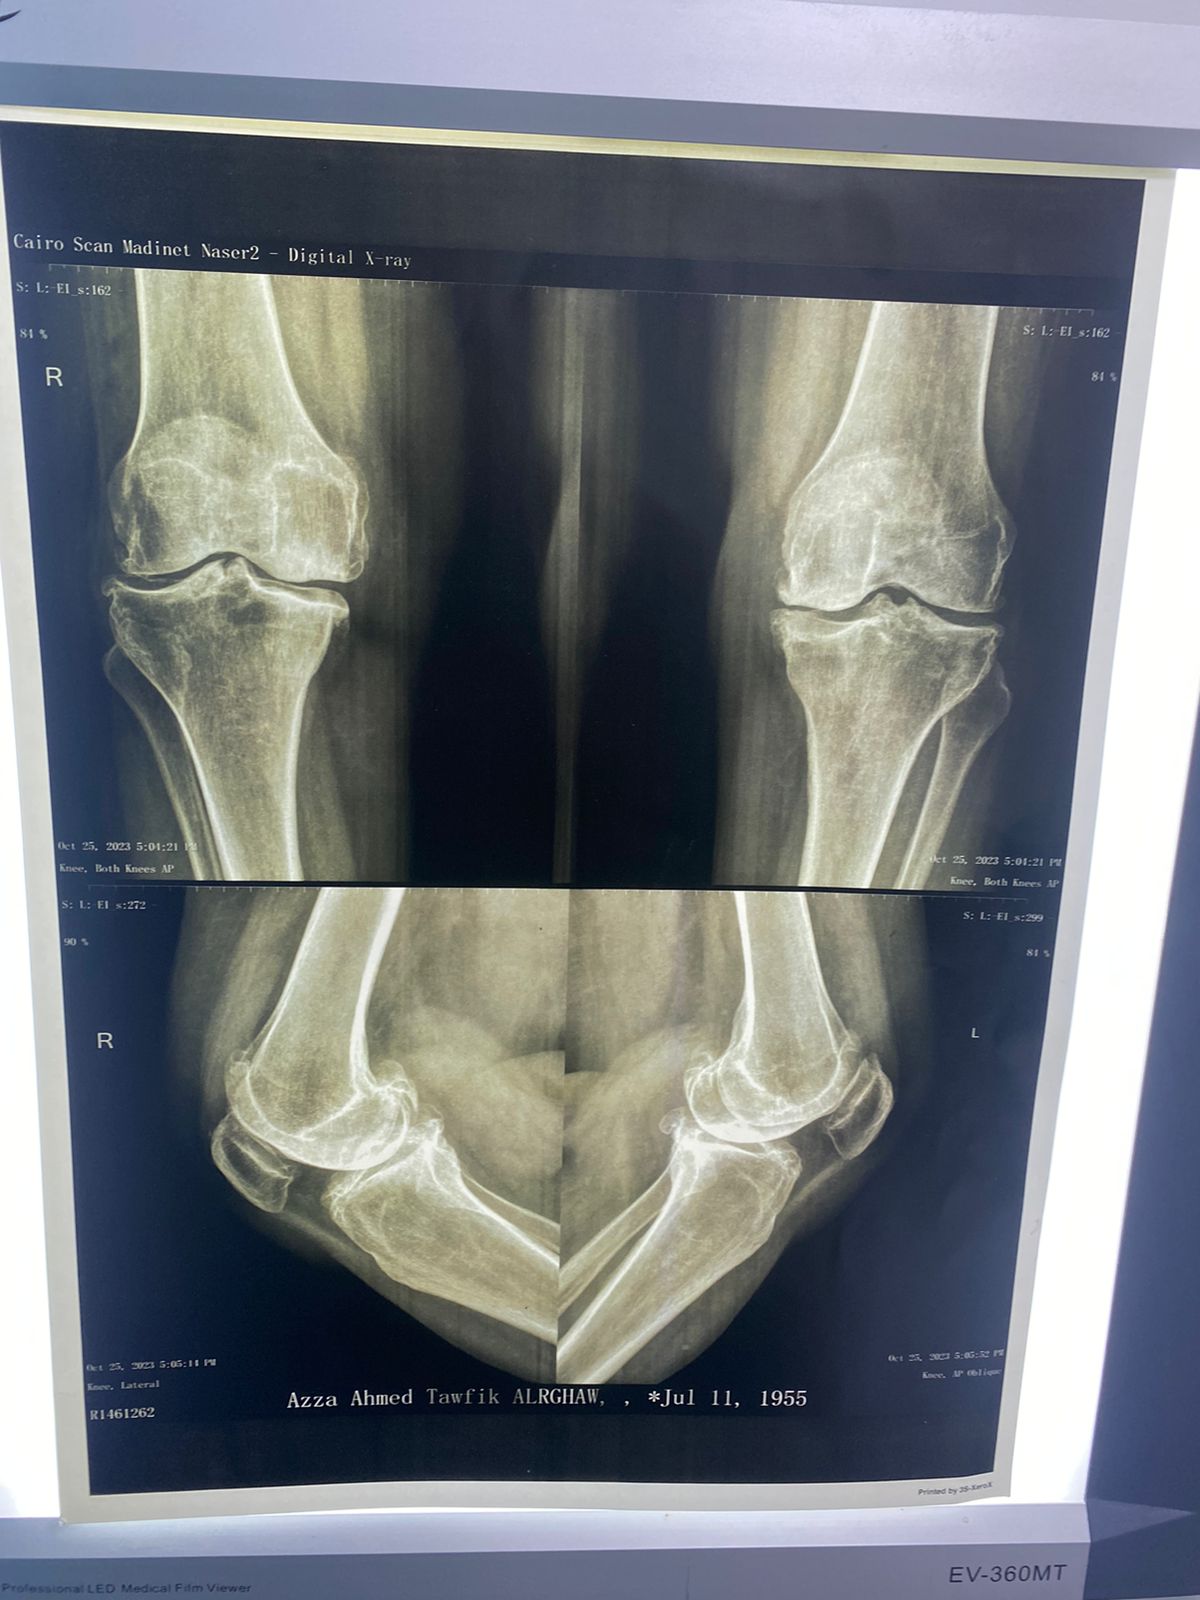

السيده/ عزه الرخاوي العمر ٦٨ عام كانت تعاني من تآكل شديد بالركبتين تم تغيير المفصل الايسر منذ ٣ أعوام تم تغيير المفصل الايمن منذ ٨ اشهر هي الآن تمشي بشكل طبيعي تماما